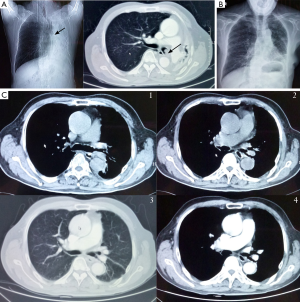

A 64-year-old man was referred to our hospital with irritating cough in September 2014. Chest CT scan showed a lesion in the terminal left main bronchus, bronchoscopy saw submucosal tumor at the end of the left main bronchus, from the carina 2.5 cm (seven cartilaginous rings), was pushed through to bronchial cavity and narrow the lumen. The opening of upper and lower lobe bronchus was observed free from involvement (Figure 1A). The diagnosis of adenoid cystic carcinoma was made on the basis of pathological findings by bronchoscopy biopsy. Surgical procedure: we used posterolateral incision through the 5th intercostal chest, breaking the 5th rib and free intercostal muscle pedicle flap. In the operative view, we first release the hilar dissect mediastinal and hilar lymph nodes. Then we fully free pulmonary vein and pulmonary artery, respectively, setting on a leash, and totally release the left main bronchus and lobar bronchus. When removing the truncus intermedius, intraoperative frozen pathological examination of tumor proximal, distal transection of the left main bronchus, and lobe bronchus showed negative. Surgical reconstruction of the second carina was performed on continuous suture upper and lower lobe bronchus side-to-side like ‘B’ type, and then make the left main bronchus anastomosis end-to-end with 3-0 Prolene. Intercostal muscle pedicle flap was surrounded the anastomosis and suture fixation at last (Figure 1B,C). Since the results of a final pathological examination showed the upper lober margin was positive, the postoperative adjuvant radiotherapy was performed 6 weeks later.